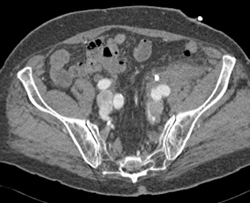

Psoas Abscess